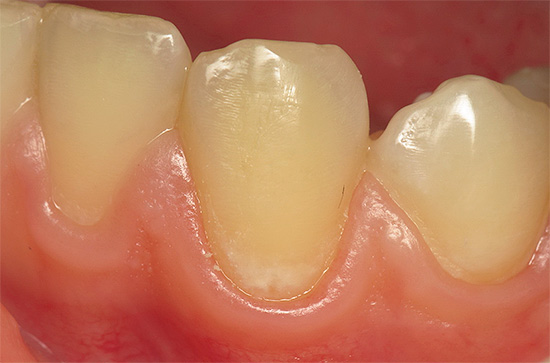

Nella maggior parte dei casi, il paziente non può riconoscere la carie dello smalto nelle prime fasi, poiché la clinica di questa patologia è scarsamente espressa. Quando appare un punto bianco o pigmentato, molti lo attribuiscono alla placca o al tartaro, non capendo la gravità del problema.

Il colore dello smalto interessato può essere diverso, a seconda delle caratteristiche del cibo assunto regolarmente e della presenza di alcuni coloranti in esso.

Nella foto sotto, la carie di smalto è presentata come la fase iniziale della lesione con segni caratteristici di questa particolare fase: